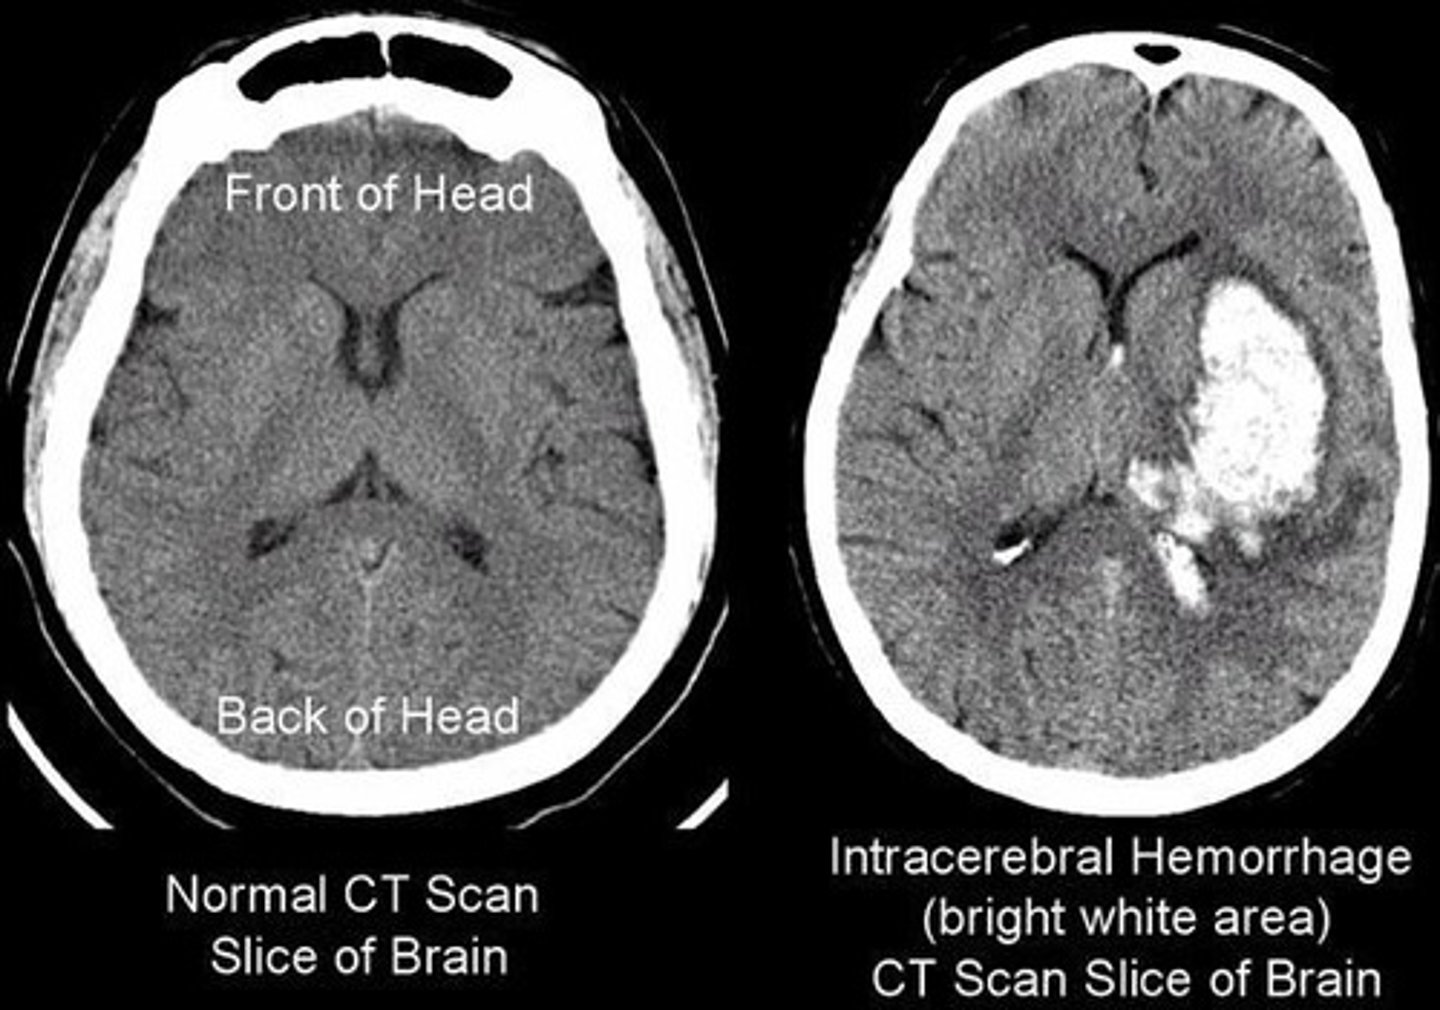

What imaging techniques are utilized in biophysics?

X-ray imaging, ultrasound sonography, and computed tomography (CT) scans.